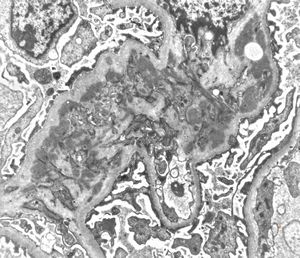

M,53y. | type III membranoproliferative glomerulonephritis